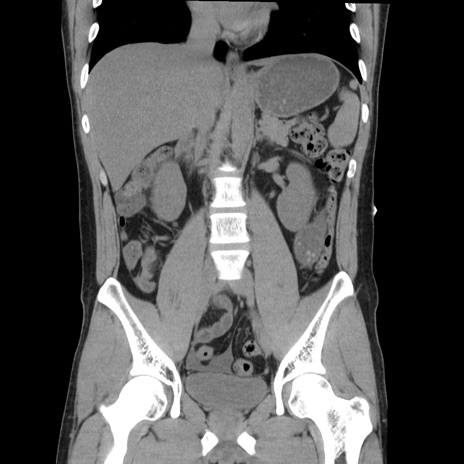

症例36(冠状断像)

【症例】20歳代 男性

【主訴】心窩部痛

【現病歴】今朝より上腹部痛あり。一旦軽快していたが再度出現したため救急要請。昨日夕に白身の魚を含む刺身を食べた。

【身体所見】BP 136/89mmHg、HR 74/min、BT 37.0℃、腹部:膨満、軟、心窩部に圧痛あり。反跳痛なし、筋性防御なし、腸雑音やや亢進あり。

【データ】WBC 17700、CRP 0.48